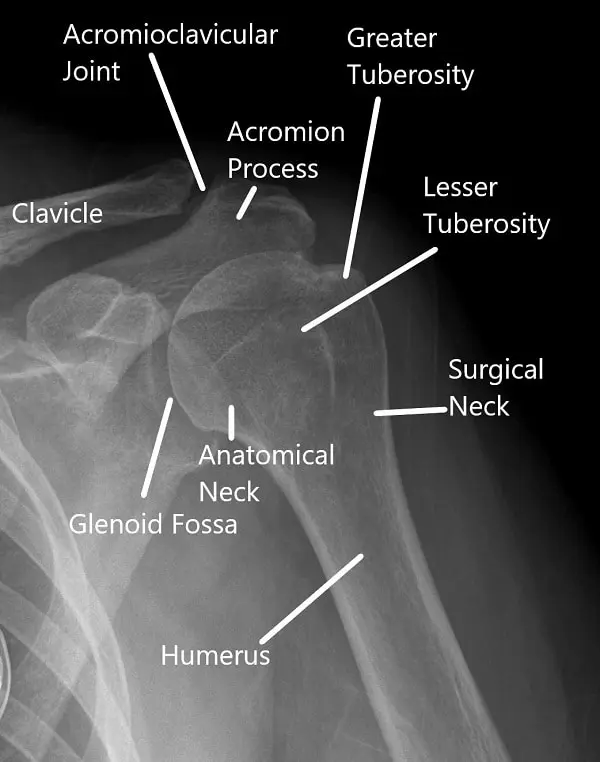

Radiografía del hombro en vista AP